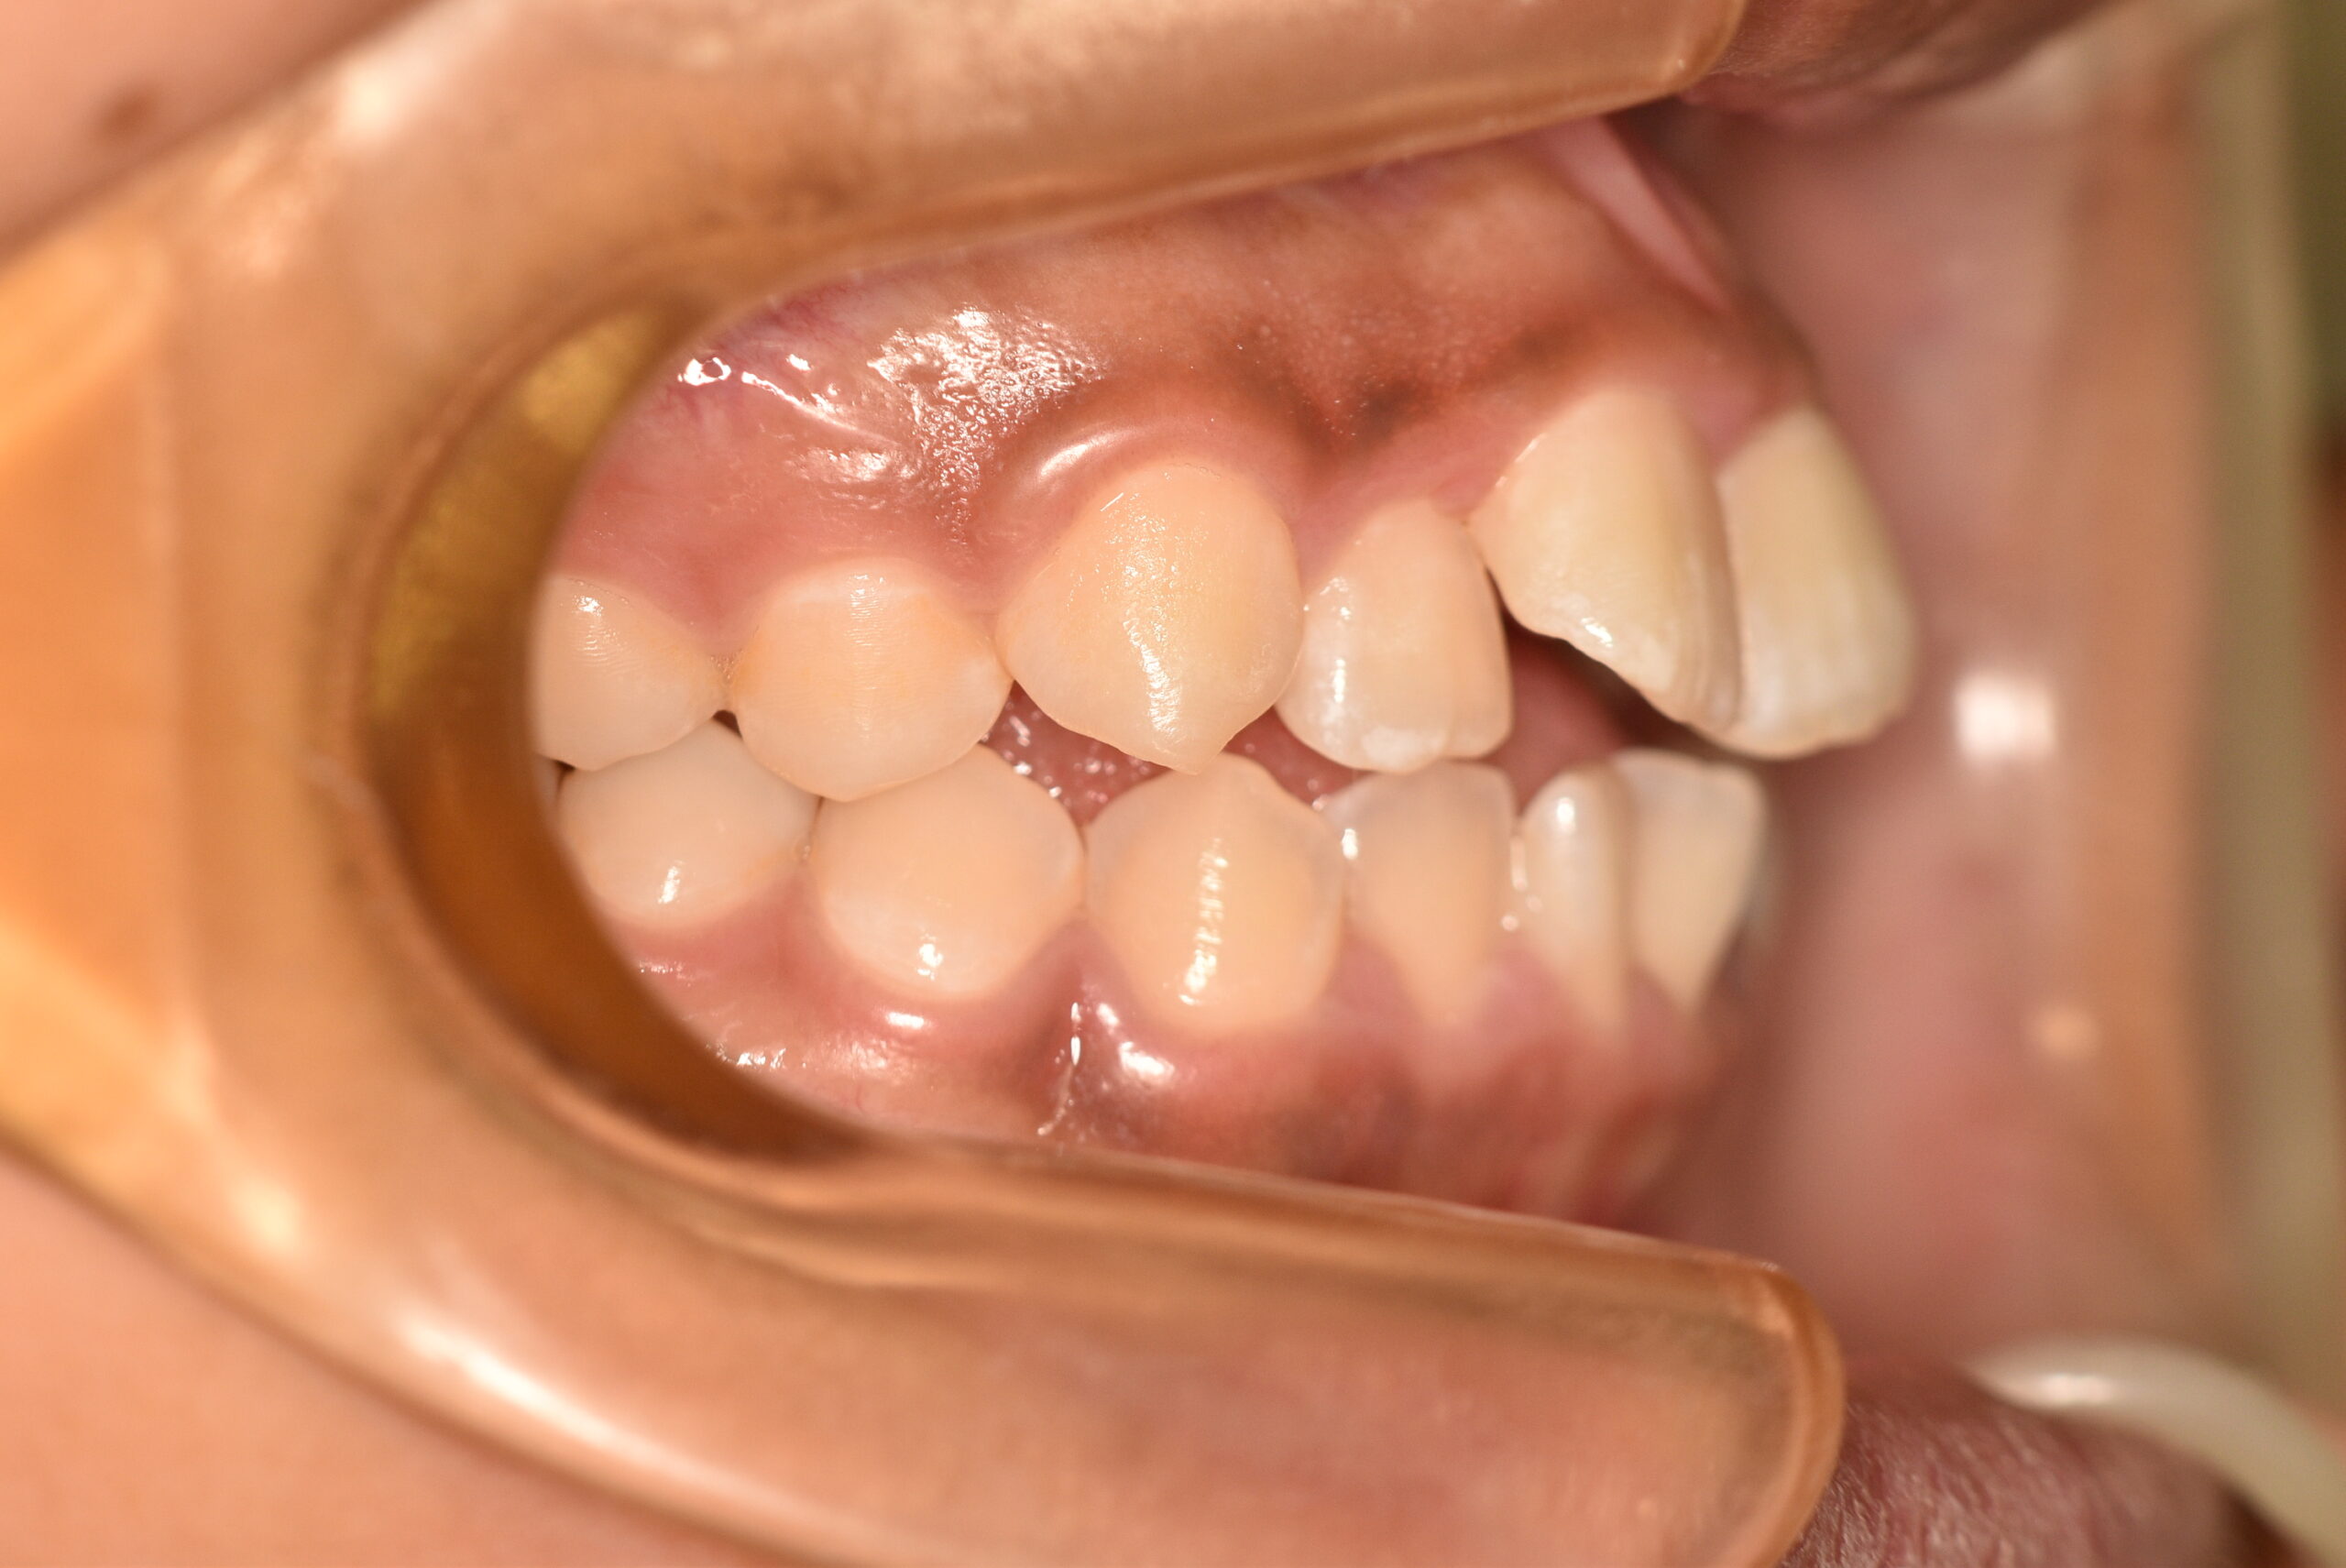

| 治療内容の詳細 | 初診時14歳の女性で、歯のがたつき、かみ合わせを気にされ来院されました。 検査の結果、上下顎前歯部叢生および開咬を伴うアングルⅠ級不正咬合と診断しました。 治療としては、非抜歯の上、セルフライゲーションブラケット装置(デーモンシステム)と マウスピース矯正装置(インビザライン)で配列を行いました。 開咬については、顎間ゴムの協力もあり改善されました。 治療期間は、2年2ヶ月でした。 |